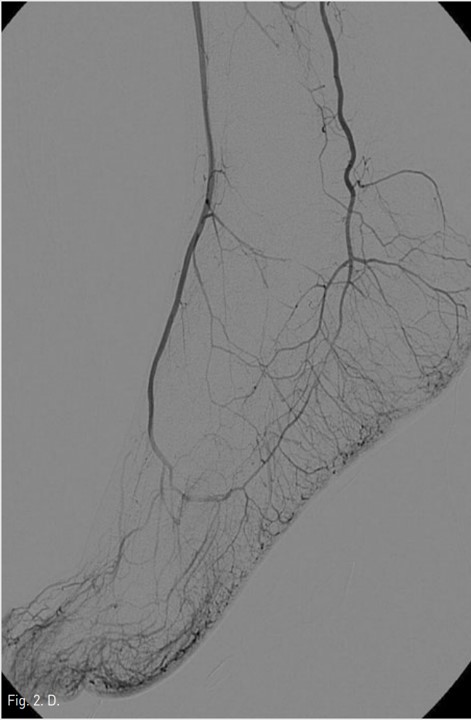

Fig. 2. D

Fig. 2C, D. Final right lower extremity angiograms show complete obliteration of pseudoaneurysm in the right common femoral artery with no embolism to the distal part of the right lower extremity arteries.